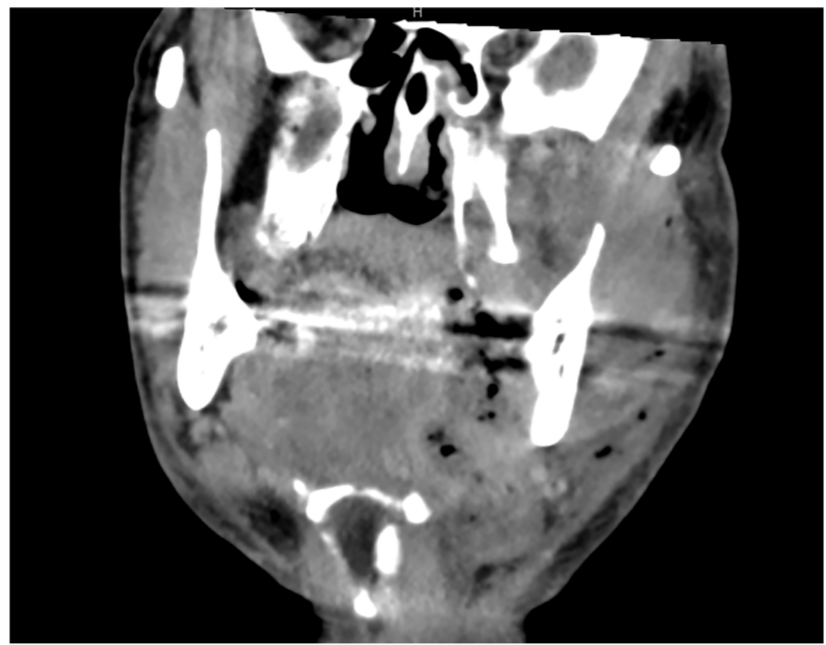

Rare Sciatic Nerve Tumor in Child Successfully Treated with Microsurgery

“This case underscores the importance of meticulous surgical technique, the potential value of IONM, and vigilant postoperative care in achieving optimal outcomes for deep-seated pediatric neurofibromas.” BUFFALO, NY — January 21, 2026 — A new case report was published in…